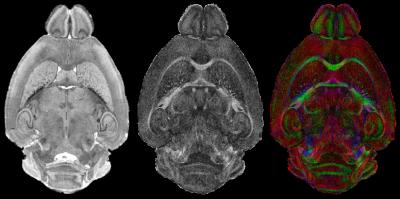

DURHAM, N.C. – The most detailed magnetic resonance images ever obtained of a mammalian brain are now available to researchers in a free, online atlas of an ultra-high-resolution mouse brain, thanks to work at the Duke Center for In Vivo Microscopy.

In a typical clinical MRI scan, each pixel in the image represents a cube of tissue, called a voxel, which is typically 1x1x3 millimeters. "The atlas images, however, are more than 300,000 times higher resolution than an MRI scan, with voxels that are 20 micrometers on a side," said G. Allan Johnson, Ph.D., who heads the Duke Center for In Vivo Microscopy and is Charles E. Putman Distinguished Professor of Radiology.

The atlas used three different magnetic resonance microscopy protocols of the intact brain followed by conventional histology to highlight different structures in the reference brain. The brains were scanned using an MR system operating at a magnetic field more than 6 times higher than is routinely used in the clinic. The images were acquired on fixed tissues, with the brain in the cranium to avoid the distortion that occurs when tissues are thinly sliced for conventional histology.

The team was also able to digitally segment 37 unique brain structures using the three different data acquisition strategies.